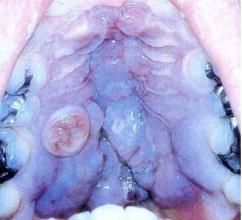

三。經典型(歐洲型) 病人多發生於50~70歲,早期損害最常見於下肢遠端及手與前臂處,逐漸向軀幹發展。呈淡紅、淡藍黑、青紅或紫色斑或斑塊,以後增大融合形成大的斑塊或結節,結節硬如橡皮,局部腫脹,以後可發明顯的淋巴水腫。後期斑塊與結節可出現於面部、耳、軀幹及口腔,特別是在軟齶較多見,病情緩慢進行時可出現新結節,常自發出血或外傷後出血,並逐漸增大,可發生潰瘍,甚至發生壞疽,需要截肢。然而特別是早期,也可出現緩解期,幾乎所有結節均自然消退,遺留萎縮及瘢痕。伴有瘙癢、燒灼或疼痛。

卡波西肉瘤 2.主要症狀及體徵:在未患愛滋病的老年人其卡波西肉瘤通常發生於足趾及腿部,表現為紫色、暗褐色斑塊或結節,呈真菌樣生長或浸潤軟組織及侵犯骨組織,約5%~10%會有淋巴結和內臟的播散。伴有愛滋病的病人其卡波西肉瘤可能是首發症狀,僅僅表現為隆起的紫色、粉紅色或紅色的丘疹或、圓形、卵圓形褐色或紫色斑塊,往往先出現在軀幹上部的皮膚或黏膜,可在皮膚上廣泛播散,並伴有內臟損害及淋巴結轉移,可能會有廣泛出血包括內臟出血